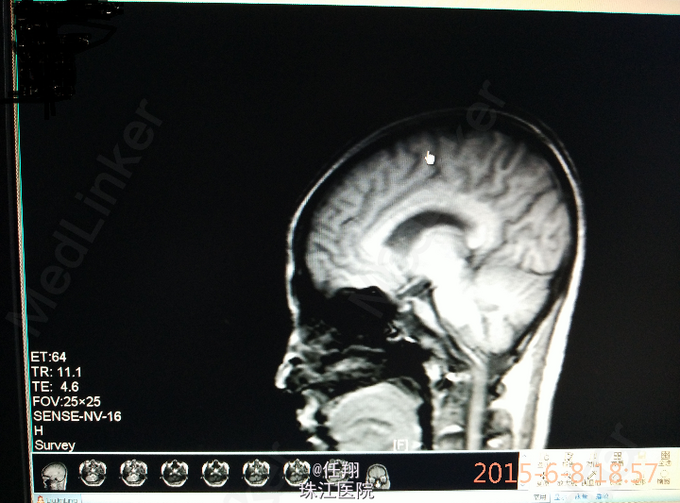

血常规、及生化指标基本正常,血沉:21mm/h,颅脑MRI:右侧额叶底部中线旁软化灶伴周围胶质增生改变,左侧海绵窦后方及鞍背后方见多发异常信号影,呈轻中度不均质强化,斜坡脑膜增厚强化,较前次片无明显改变,建议增强扫描进一步观察;双侧额顶叶皮层下、右侧放射冠多发腔隙性脑梗塞及缺血灶,病灶较强缩小。

原发性中枢神经系统血管炎(primaryangiitisofthecentralnervoussystemPACNS),又称为中枢神经系统肉芽肿性血管炎(granulomatousangiitisofthecentralnervoussystem),或孤立性中枢神经系统血管炎(isolatedangiitisofthecentralnervoussystem),是一种较少见的疾病。本例患者有神经系统症状的临床表现,但无明确定位体征,病史长,激素治疗有效,停药或减药症状复现,考虑患者经济因素,未行进一步检查,在结合临床症状及颅脑MRI的结果,诊断PACNS并治疗有效,嘱患者定期复查。